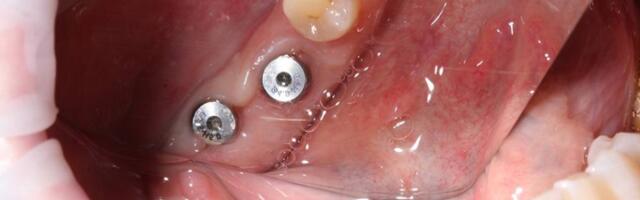

Что происходит с имплантатом в первые 3 секунды после установки

Меня зовут Игорь Кузьмин, я врач стоматолог-хирург, дентальный имплантолог, эксперт компании Alpha-Bio Tec. Моя работа — изучать и работать с поверхностями дентальных имплантатов на уровне, который не разглядеть без электронного микроскопа. Часто успех имплантации списывают исключительно на мастерство хирурга, и это действительно крайне важно. Но я хочу рассказать о другом — о тихой битве, которая разворачивается на границе «титан-кость» в первые мгновения после установки. От её исхода зависит, приживется л